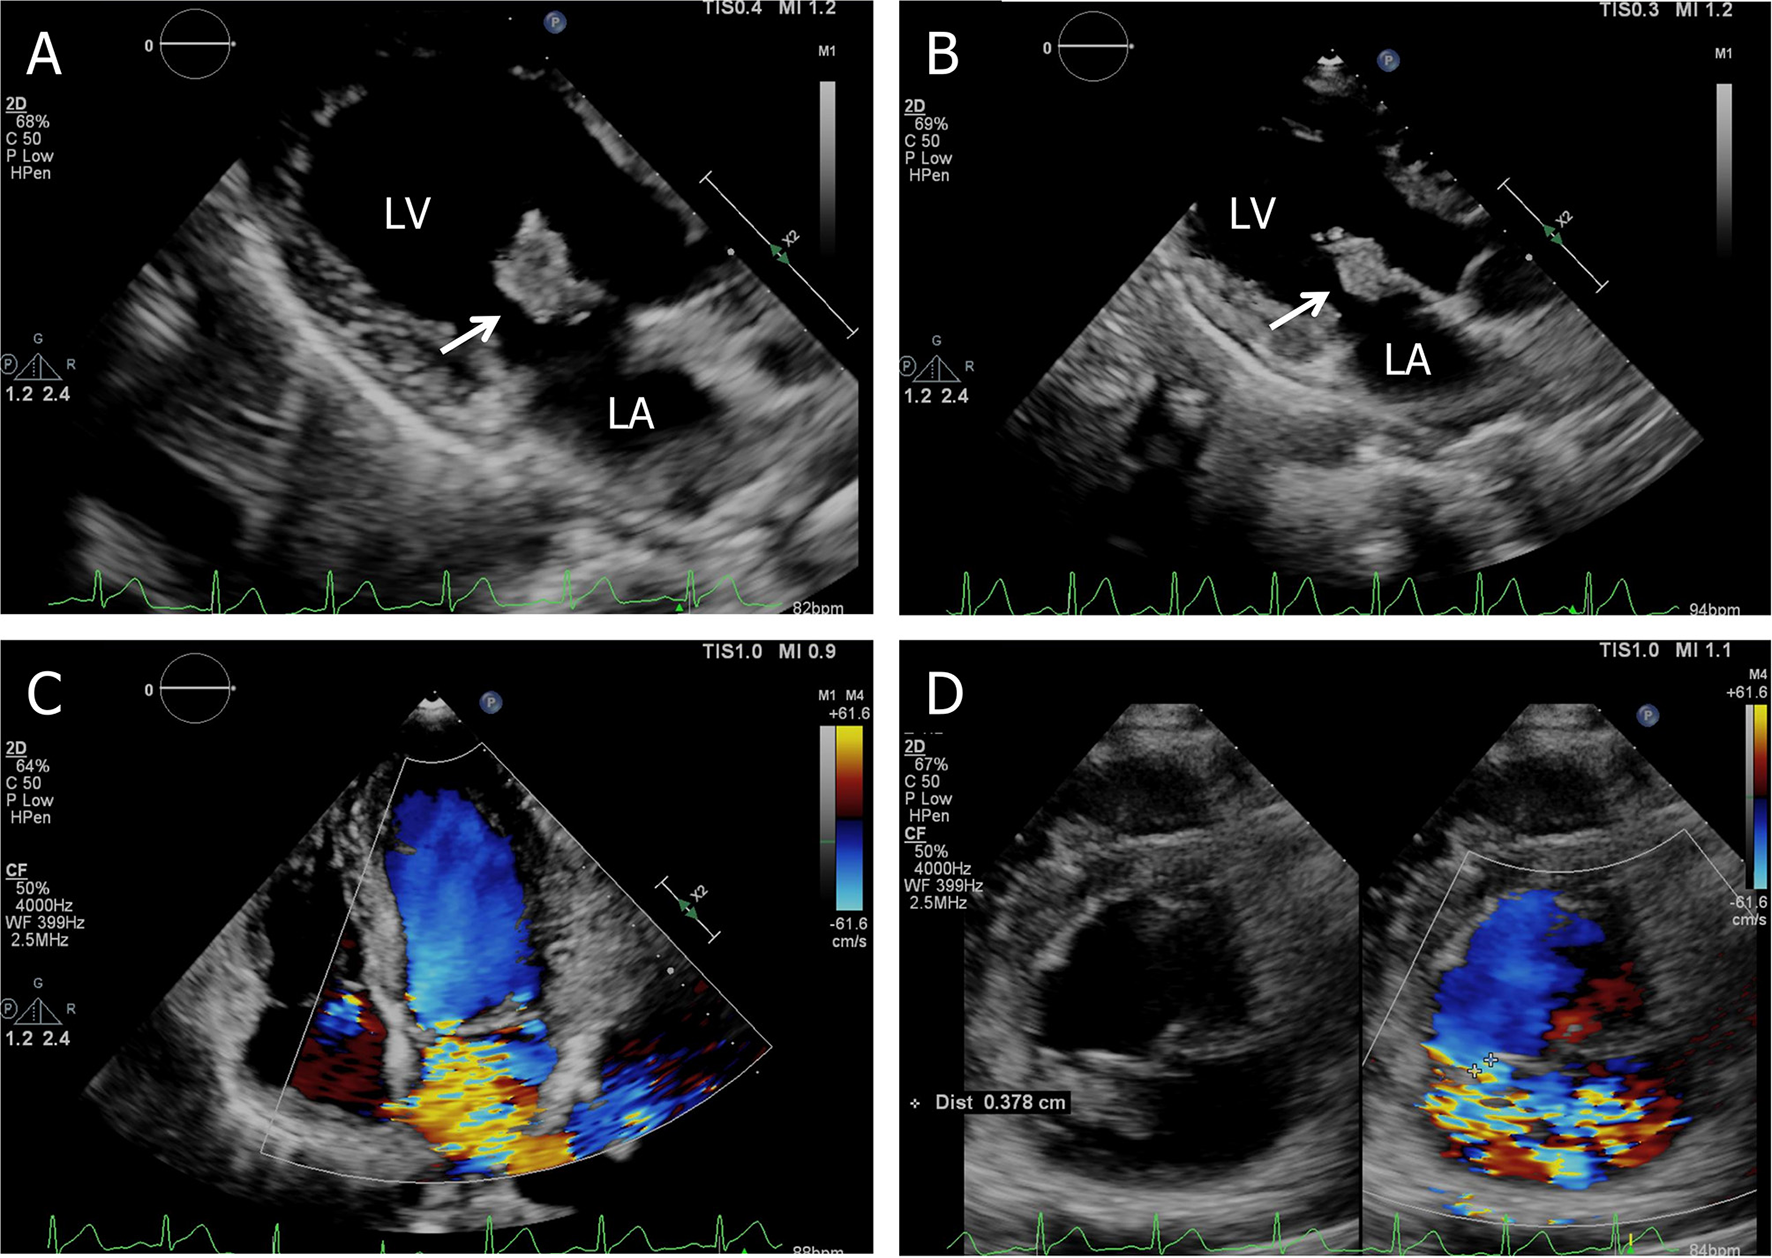

On admission, with a presumptive diagnosis of IE, physical examination showed a grade 4/6 systolic murmur over the mitral area upon auscultation and obvious splenomegaly via palpation. No Janeway's lesions, Osler's nodes were observed. Laboratory studies revealed normocytic anemia (hemoglobin 10.8 g/dl, normal range: 13.0–17.5 g/dl), normal leukocytes but elevated C-reactive protein of 30.61 mg/l, and erythrocyte sedimentation rate of 38 mm in the first hour. TTE confirmed isolated vegetation of 2.24 cm2 on the anterior mitral valve leaflet, with valve perforation and severe mitral regurgitation (Figure 1).

Figure 1

Transthoracic echocardiogram. (A) Apical three-chamber view shows a 2.24 cm2 vegetation in the anterior leaflet of the mitral valve, (B) the size of the vegetation decreased to 1.91 cm2 on the 7th hospital day, (C) apical four-chamber view shows severe mitral regurgitation, and (D) short-axis parasternal view shows severe mitral regurgitation contrasted with color Doppler. LA, left atrium; LV, left ventricle.